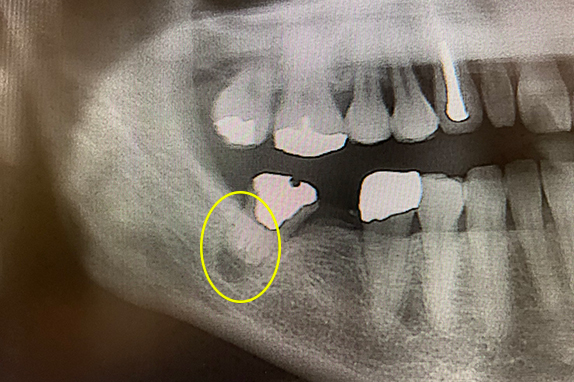

1. 歯周再生療法+インプラント治療術前

2. 歯周再生療法+インプラント治療術後

• 主訴

左で噛めない(50代女性)

• 回数期間

約8ヶ月

• 治療法

歯周再生療法+インプラント治療

• 治療費用

約50万円(税抜)

左側で噛めないという主訴で来院。左上6番にインプラントを埋入し、7番を歯周再生療法で骨移植をしたケースです。

<リスク・副作用>

術後は顔面の腫脹に加え、青あざができる場合があります。過度な衝撃や咬合を加えると補綴物の破折、脱落の可能性があります。